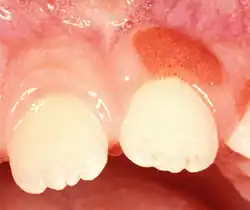

Plasma cell gingivitis in an adult (histologically verified).

Plasma cell gingivitis in 7-year-old child. Histologically verified.

Plasma cell gingivitis in a 10-year-old child. Histologically verified.

Plasma cell gingivitis appears as mild gingival enlargement and may extend from the free marginal gingiva on to the attached gingiva.[6] Sometimes it is blended with a marginal, plaque induced gingivitis, or it does not involve the free marginal gingiva. It may also be found as a solitude red area within the attached gingiva (pictures). In some cases the healing of a plaque-induced gingivitis or a periodontitis resolves a plasma cell gingivitis situated a few mm from the earlier plaque-infected marginal gingiva. In case of one or few solitary areas of plasma cell gingivitis, no symptoms are reported from the patient. Most often solitary entities are therefore found by the dentist.[2]

The gums are red, friable, or sometimes granular, and sometimes bleed easily if traumatised.[6] The normal stippling is lost.[7] There is not usually any loss of periodontal attachment.[6] In a few cases a sore mouth can develop, and if so pain is sometimes made worse by toothpastes, or hot or spicy food.[7] The lesions can extend to involve the palate.[7]